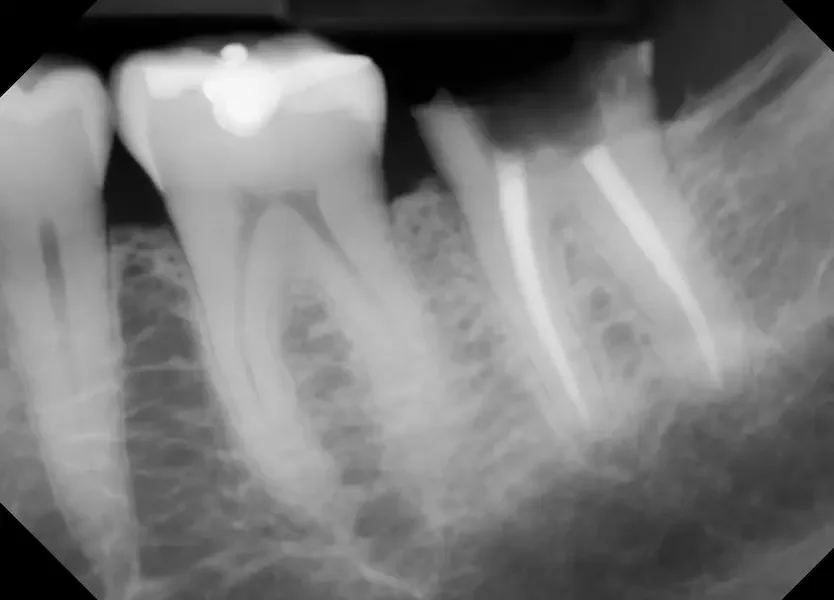

Dr Brayden Teuscher details a REAL extraction and bone graft case at Teuscher Legacy Dental. Including how the healing should look 1 week after the procedure. See the full case in our blog post.

The day your tooth is extracted, we fill the space where the roots used to be (the socket) with bone graft material. Here’s more detail on exactly how the socket preservation procedure goes, featuring a real case at Teuscher Legacy Dental.

The biggest reason to get a socket preservation bone graft is if you plan on a dental implant in the future. Sometimes it isn’t necessary. Here’s a guide on how to decide whether you want a socket preservation bone graft or not.

Socket preservation is a bone graft placed into the empty tooth socket immediately after an extraction. Usually a thin collagen membrane covers the graft and the site is sealed. This helps the jaw keep its shape while new bone replaces the graft over the next few months.

Why it matters: without a bone graft, the ridge naturally shrinks which can complicate implants and compromise smile esthetics.